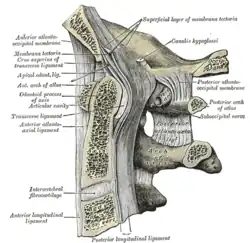

Anterior arch

The anterior arch forms about one-fifth of the ring: its anterior surface is convex, and presents at its center the anterior tubercle for the attachment of the Longus colli muscles and the anterior longitudinal ligament; posteriorly it is concave, and marked by a smooth, oval or circular facet (fovea dentis), for articulation with the odontoid process (dens) of the axis.

The upper and lower borders respectively give attachment to the anterior atlantooccipital membrane and the anterior atlantoaxial ligament; the former connects it with the occipital bone above, and the latter with the axis below.[5]

Posterior arch

The posterior arch forms about two-fifths of the circumference of the ring: it ends behind in the posterior tubercle, which is the rudiment of a spinous process and gives origin to the Recti capitis posteriores minores and the ligamentum nuchae. The diminutive size of this process prevents any interference with the movements between the atlas and the skull.

The posterior part of the arch presents above and behind a rounded edge for the attachment of the posterior atlantooccipital membrane, while immediately behind each superior articular process is the superior vertebral notch (sulcus arteriae vertebralis). This is a groove that is sometimes converted into a foramen by ossification of the posterior atlantooccipital membrane to create a delicate bony spiculum which arches backward from the posterior end of the superior articular process. This anatomical variant is known as an arcuate foramen.

This groove transmits the vertebral artery, which, after ascending through the foramen in the transverse process, winds around the lateral mass in a direction backward and medially to enter the vertebrobasilar circulation through the foramen magnum; it also transmits the suboccipital nerve (first spinal nerve)

On the under surface of the posterior arch, behind the inferior articular facets, are two shallow grooves, the inferior vertebral notches. The lower border gives attachment to the posterior atlantoaxial ligament, which connects it with the axis.

Lateral masses

Transverse processes

The transverse processes are large; they project laterally and downward from the lateral masses, and serve for the attachment of muscles which assist in rotating the head. They are long, and their anterior and posterior tubercles are fused into one mass; the foramen transversarium is directed from below, upward and backward.